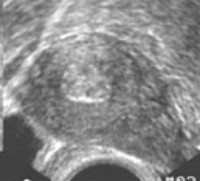

• Рентгенография лицевого скелета. На рентгенограмме видна структура с четкими контурами, которая прорастает из одного из околоносовых синусов, заполняет общий носовой ход, пространство между задней стенкой глотки и мягким небом. Деструкции костных тканей не наблюдается.

• КТ лицевого скелета. Показана при низкой информативности рентгенограммы и невозможности провести дифференциальную диагностику с раковыми опухолями. Выполняется с контрастным усилением. Томография более детально отображает аналогичные рентгенографии изменения, а также подтверждает отсутствие неоваскуляризации.